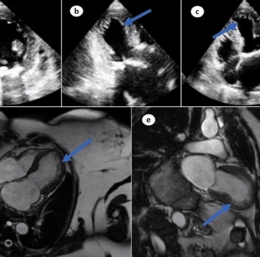

Stranski učinki | Vrhunski kardiolog alarmira zaradi poškodb srca pri cepljenih bolnikih ... Stranski učinki | Ugotovljeno je bilo, da spodbujevalci cepiva proti COVID-19 poškodujejo celice T in izklopijo naravno obrambo telesa pred okužbami in rakom ... Stranski učinki | Cepljeni proti Covidu s cepivi mRNA pod UV-svetlobo oddajajo nenavaden fluorescentni sij ... Stranski učinki | Slavni igralec doživel srčni infarkt - Prejel je vsa cepiva, mediji trdijo, da je napad povzročil ugriz gosenice ... Stranski učinki | 70 % balzamirjev je poročalo, da so od sredine leta 2021 našli nenavadne krvne strdke ... Stranski učinki | Strokovnjaki opozarjajo, da britanska nacionalna zdravstvena služba trpi za "najhujšo srčno krizo ki je ne pomnejo" ... Stranski učinki | Pričakovana življenjska doba v ZDA po cepivu proti COVID-19 zdaj upada ... Stranski učinki | Znanstveniki opozarjajo, da bi se "bolezen zombi jelenov" lahko razširila na ljudi ... Stranski učinki | Britanski nogometaš se je po zastoju srca zgrudil na igrišču ... Stranski učinki | British Telegraph: "Milijoni cepljenih ljudi imajo zdaj VAIDS - sindrom imunske pomanjkljivosti, pridobljen s cepivom" ... Stranski učinki | Italija objavlja osupljive dokaze, ki kažejo, da cepiva proti covidu mRNA povzročajo 'obsežno poškodbo možganov' pri prejemnikih ... Stranski učinki | Zdravniki pričajo: Cepljeni proti COVIDu zdaj trpijo za psihozami, anksioznostjo, halucinacijami ... ... Stranski učinki | 'Zaskrbljujoče': Število srčnih infarktov v Avstraliji rekordno visoko ... Stranski učinki | V cepljeni Avstraliji kirurgi ženski iz možganov odstranili 8 centimetrov dolgega črva ... Stranski učinki | Srce po cepljenju napihnjeno kot balon: zdravila za gensko terapijo povzročajo redko obliko kardiomiopatije ... Stranski učinki | Več kot 94 % vseh primerov gobavosti bolnikov je med "cepljenimi" ... Stranski učinki | Wi-Fi in druga elektromagnetna polja so lahko povezana z neplodnostjo in spontanim splavom ... Stranski učinki | FBI in CIA na Wikipediji prikrivata podatke o krvnih strdkih po cepljenju proti covidu ...